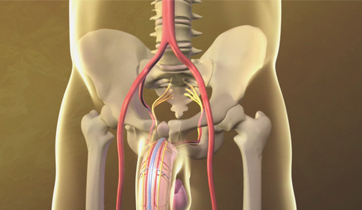

Erectile Dysfunction

Medtronic Corporation

This animationis intended to explain Erectile Dysfunction to physicians. It shows the vessels and nerves involved in blood flow obstruction to the penis, and the erectile tissue's failure to enlarge. The animation also suggests the benefits of clearing the obstruction by using stents.